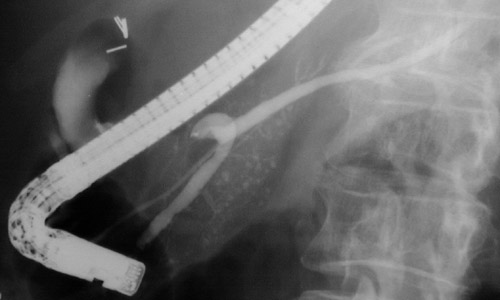

| On endoscopic retrograde pancreatography (ERCP), parenchymal calcifications can be seen but the pancreatic duct is not dilated, with even caliber and smooth outlines, suggesting a cause for pancreatitis such as a drug, viral infection, toxin, or idiopathic condition that affects mainly the parenchyma. |